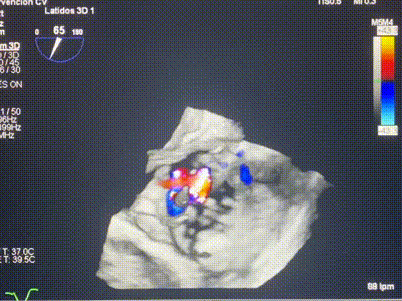

近日,西班牙阿爾瓦羅昆奎羅醫(yī)院 (Hospital Álvaro Cunqueiro)Rodrigo Estévez-Loureiro教授團隊成功應(yīng)用LuX-Valve Plus經(jīng)血管三尖瓣置換系統(tǒng)為一例因三尖瓣大量反流導(dǎo)致的右心衰竭患者完成三尖瓣置換手術(shù),術(shù)后超聲顯示人工三尖瓣植入穩(wěn)定,瓣葉啟閉良好,僅殘余微量瓣周漏?;颊咴谑中g(shù)室即刻拔除氣管插管,血流動力學(xué)改善顯著。此次手術(shù)也是LuX-Valve Plus于西班牙的首次臨床應(yīng)用,治療效果優(yōu)異。

LuX-Valve Plus經(jīng)血管三尖瓣置換系統(tǒng)此次“出海”圓滿完成,術(shù)后Rodrigo Estévez-Loureiro教授對LuX-Valve Plus經(jīng)血管三尖瓣置換系統(tǒng)的器械性能和治療效果大為稱贊,認為LuX-Valve Plus的手術(shù)體驗非常好。術(shù)后即刻超聲顯示三尖瓣反流幾乎完全消失,血流動力學(xué)改善顯著,患者恢復(fù)快。在面對復(fù)雜解剖結(jié)構(gòu)、超聲影像質(zhì)量不佳、有起搏導(dǎo)線干擾時,Lux-Valve Plus也體現(xiàn)了極強的適應(yīng)性。Thomas Modine教授和Anson Cheung教授也肯定了LuX-Valve Plus術(shù)中操作的便捷性,認為LuX-Valve Plus容錯率高,對術(shù)中影像的依賴較小,后期希望可以更多的應(yīng)用LuX-Valve Plus三尖瓣置換系統(tǒng)于臨床實踐,讓更多的三尖瓣重度反流患者盡早獲益,改善預(yù)后。

LuX-Valve Plus經(jīng)血管三尖瓣置換系統(tǒng)是我國擁有完全自主知識產(chǎn)權(quán)的心臟瓣膜介入治療產(chǎn)品,在全球范圍內(nèi)率先引用“非徑向支撐力”和“室間隔固定”的設(shè)計理念(即采用貼靠支撐和室間隔錨定的方式進行人工瓣膜的固定),能更好適應(yīng)三尖瓣結(jié)構(gòu)菲薄脆弱的特性,并且采用經(jīng)頸靜脈入路的方式,對患者的損傷進一步減小。目前,LuX-Valve Plus全國多中心FIM研究已全部完成入組,LuX-Valve Plus全國多中心確證性臨床研究已開始患者入組;此外,LuX-Valve Plus全球救治性臨床研究已成功在美國、加拿大、法國、德國、西班牙開展,并還在持續(xù)推進中,我們相信更多的三尖瓣重度反流患者將因此獲益。